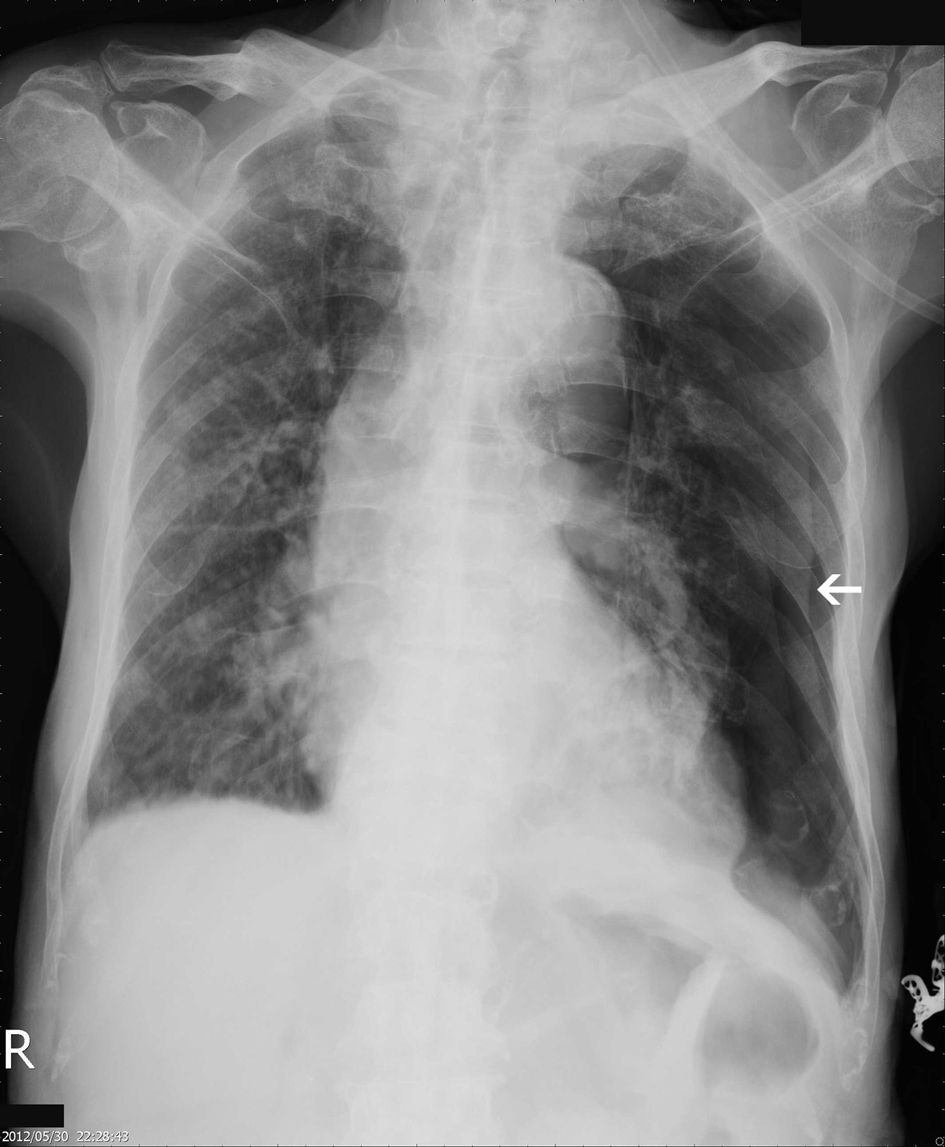

An 82-year-old male patient presented with chest tightness and shortness of breathing for 10 days. His past medical history included hypertension and old pulmonary tuberculosis. He suffered from productive cough for weeks and was referred to our center because of the worsening symptoms of dyspnea and lower leg edema noted over the past few days. On presentation, his consciousness was alert. Body temperature was 37.8 °C. Pulse was 136 per minute regular. Blood pressure was 164/90 mmHg. Oxygen saturation was 88%. Auscultation revealed decreased breathing sounds at left lung field and sonorous rhonchus at right lung field. X-ray of the chest showed left pneumothorax with collapse of left lung, and ground glass opacities in right lung field (Fig. 1), more in favor of inflammatory process at that time. He was admitted under the impression of right lung pneumonia with left pneumothorax and received chest tube insertion and empiric antibiotics treatment. However persistent air leak noted, he then received a chest CT for further survey. A chest CT showed nodular lesions over bilateral lung, with diffuse bone, left lower neck (Fig. 2), left suparclavicular, mediastinum, as well as right hilar (Fig. 3) and lower abdominal lymph nodes metastases. Unknown primary malignancy with bilateral lung metastases, diffuse bony metastases with left supraclavicular and left neck lymph node metastases was impressed and further tissue proof for possible underlying malignancy was recommended. For this reason, an echo guided biopsy with left neck lymph node biopsy was arranged for further study because the surgical intervention was not recommended for the patient due to poor lung function while patient declined bronchoscopy biopsy either. A subsequent neck lymph node biopsy revealed metastatic adenocarcinoma, while immunohistochemical stain for thyroid transcription factor -1(TTF-1), and cytokeratin 20 (CK20) are all negative. Serum tumor markers were examined in an attempt to identify the primary lesion, revealing a PSA level of > 1,000 ng/mL (normal < 4.0 ng/mL) while CEA 2.7 ng/mL (normal < 5.0 ng/mL). Digital rectal examination showed an enlarged and hardened left prostate lobe. An abdomen CT disclosed 4.3 × 3.0 cm ill defined heterogenous mass lesion at lower lobe of prostate (Fig. 4a) with regional and non-regional lymph nodes (Fig. 4b) and bony metastases. The urologist was consulted, and transrectal ultrasonography (TRUS) showed irregular urinary bladder wall thickening with enlargement of prostate, hypoechoic nodule with increased vascularity in left peripheral zone of prostate. Meanwhile the patient refused further tissue proof due to his poor general condition. The pathologist was informed of the elevated serum PSA and further clinical data, then an additional immunohistochemical staining of the left neck lymph node biopsy with P504S was performed as was compared to the regular H&E stain (Fig. 5a), the neoplastic cells expressed P504S diffusely (Fig. 5b), a metastatic adenocarcinoma of prostatic origin was confirmed. However his condition went downhill rapidly, and after thoroughly discussion with the patient and his family, they decided to receive hospice care and refused further intervention.

![]() Click for large image | Figure 1. Initial CXR showing left pneumothorax, with ground grass densities over right lung. |